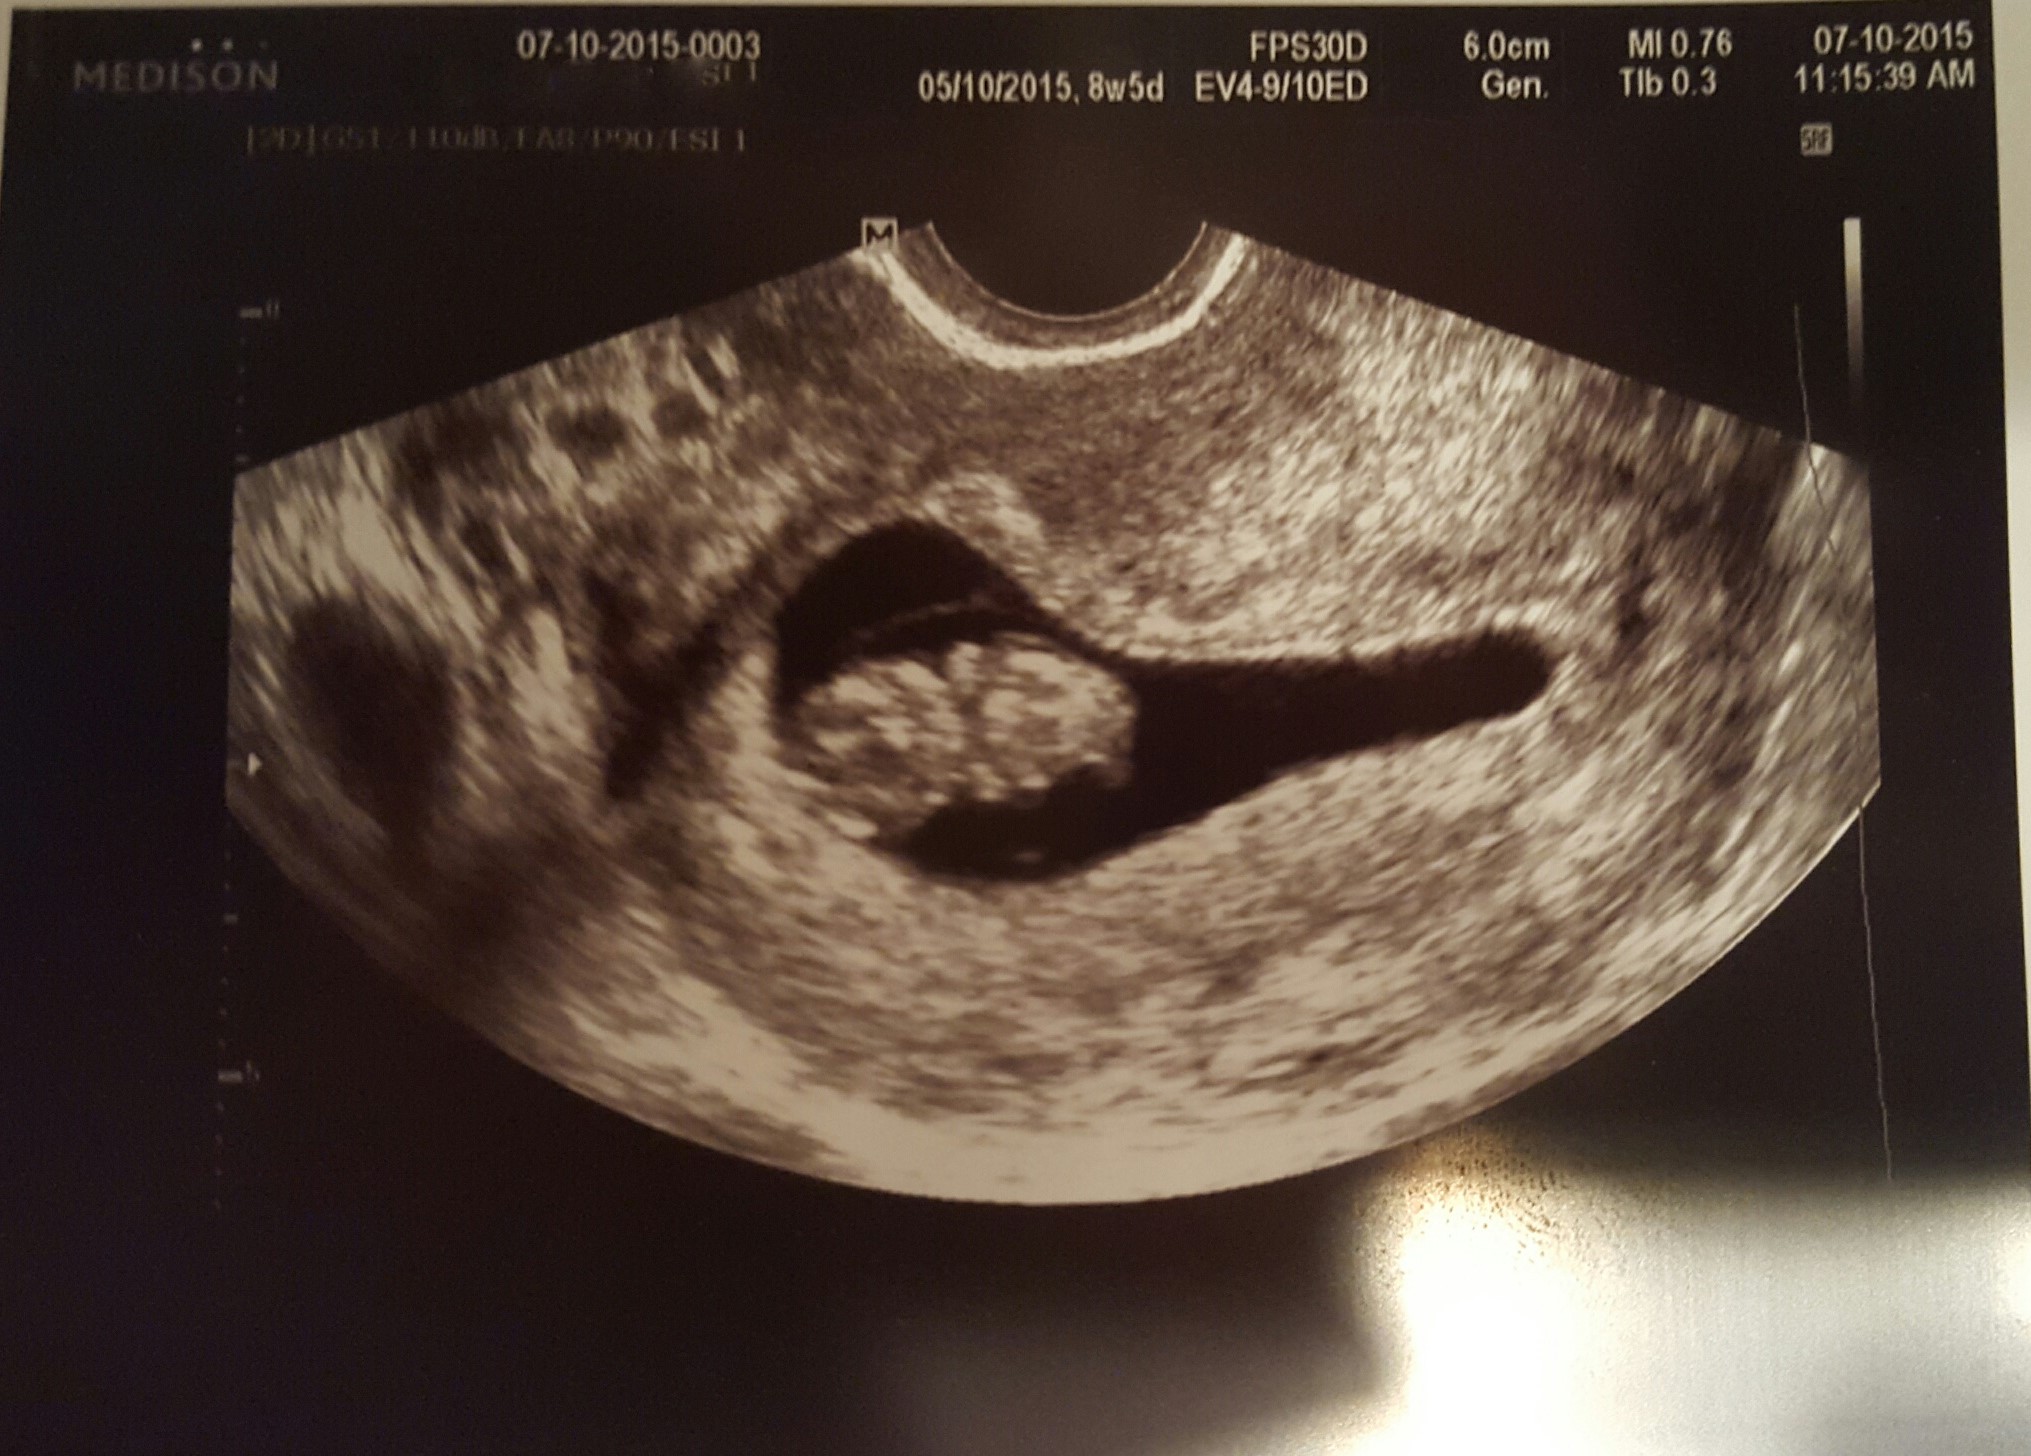

I know this method is about as accurate as holding a ring over your stomach and taking a guess... Curiosity is taking over me while I wait for the 12 weeks scan though :) I know it was trans vaginal and I took a look at my others, 2 out of the 3 others matched up. The third one was a profile so I'll never know. Just for the fun of it... What would you guess if you were in my shoes?

Attachment 26215